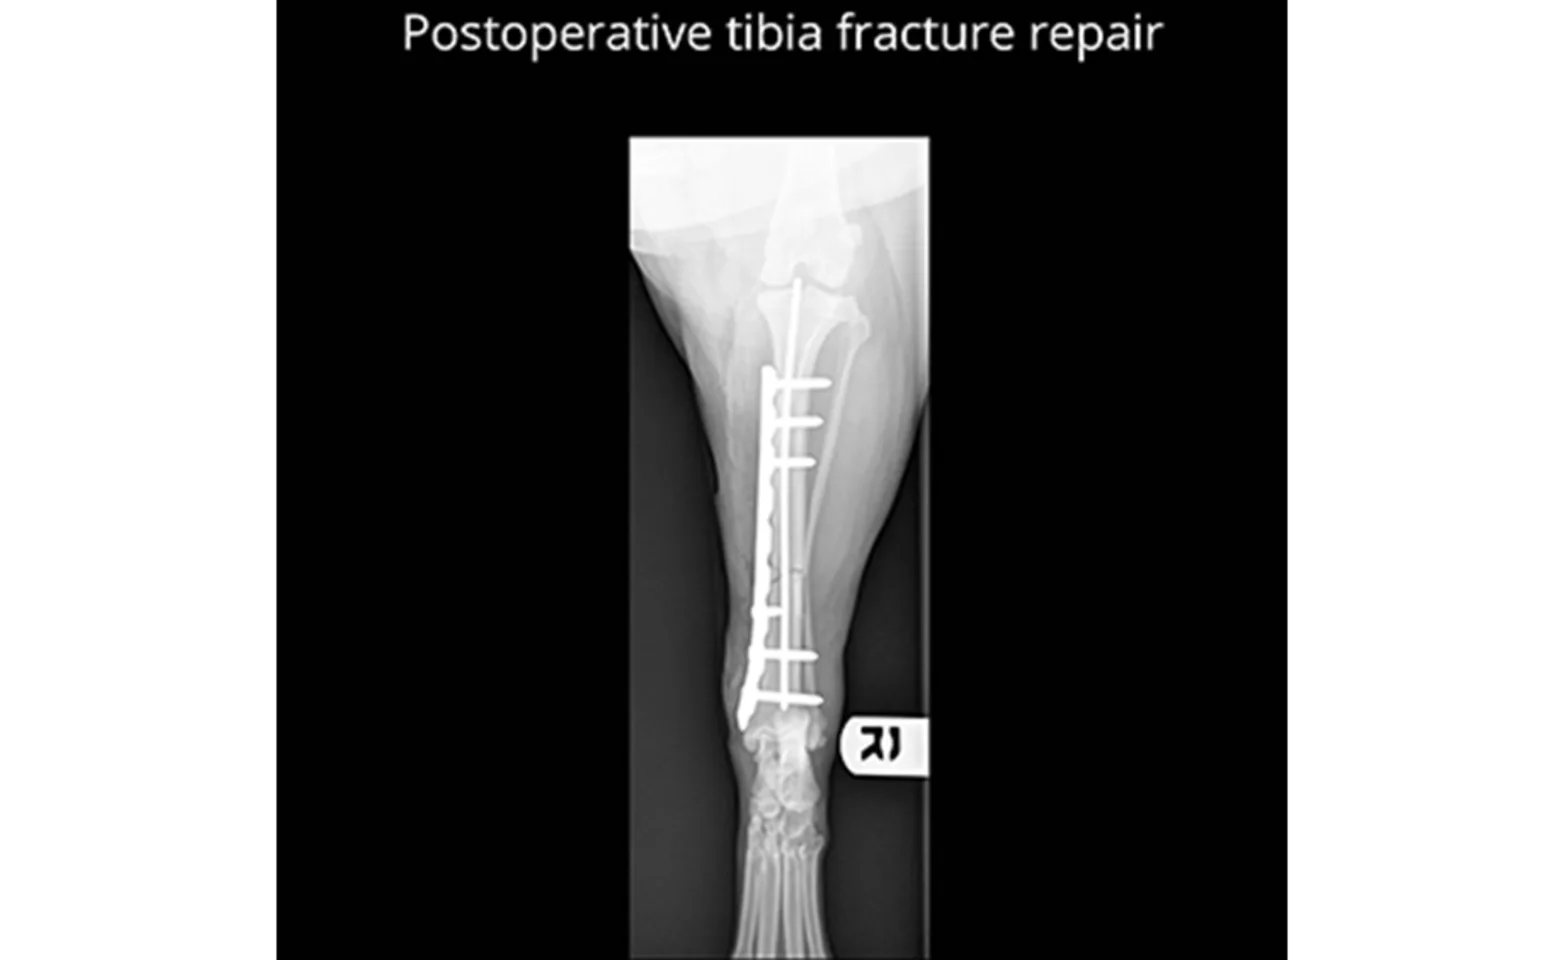

A fracture can seem like a devastating injury for your pet. Fortunately, the majority of fractures are fixable and carry a good long-term prognosis. The method of fracture repair will depend on the bone or bones that are involved. The most common methods of fracture stabilization are performed with bone plates, screws, and pins. The average time for a fracture to heal is about 8-10 weeks but may be shorter for young patients, or slightly longer for geriatric patients. More recently, certain fractures are being repaired in a minimally invasive fashion. This method uses intra-operative imaging, called fluoroscopy, to evaluate the bone while it is being aligned and stabilized with implants. With the use of fluoroscopy, incisions can be much smaller and the blood supply to the bone is better preserved. This type of fracture repair is usually referred to as “Minimally Invasive Plate Osteosynthesis” or “MIPO”.